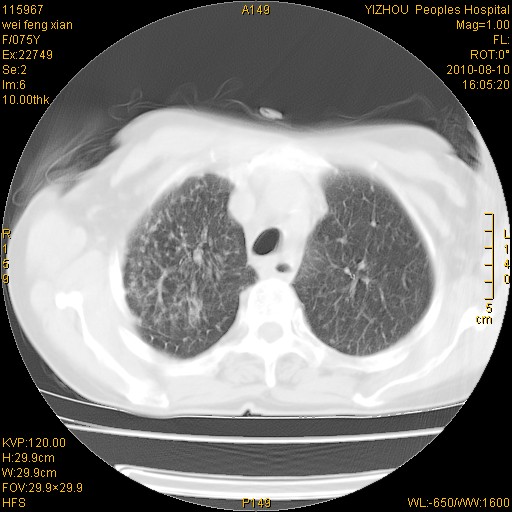

标题: CT28313:两肺弥漫性病变 [打印本页]

标题: CT28313:两肺弥漫性病变

女,75岁,患者反复头昏乏力面色苍白3年,再发10天入院。临床贫血查因。

双肺间质增生并右肺上叶炎性改变,不除外右肺上叶结核病肺内播散

考虑慢支伴右上肺慢性感染可能性大,建议结合临床排外尘肺可能。

考虑尘肺可能性大.

考虑右肺上叶炎症合并双肺结核可能性大,建议上传纵隔窗ct图片。

双肺结核可能性大

考虑尘肺并结核;右上肺支气管扩张!

结核、尘肺、支气管肺泡癌都不能除外

右肺上叶继发性肺结核伴肺内血型播散!

考虑右肺上叶继发性肺结核伴两肺播散。